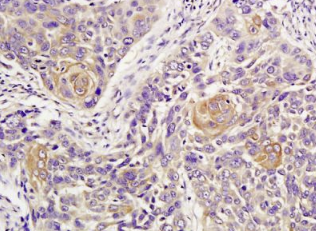

组织/细胞:人肺癌;4%多聚甲醛固定石蜡包埋;

抗原提取:柠檬酸缓冲液(0.01M,pH 6),15min煮沸,用3%过氧化氢阻断内源性过氧化物酶30min;37℃下阻断缓冲液(正常山羊血清)20 min;

孵育:抗ATM多克隆抗体,未结合(BS-1370R)1:300,4°C下过夜,然后与二级抗体结合,DAB染色。